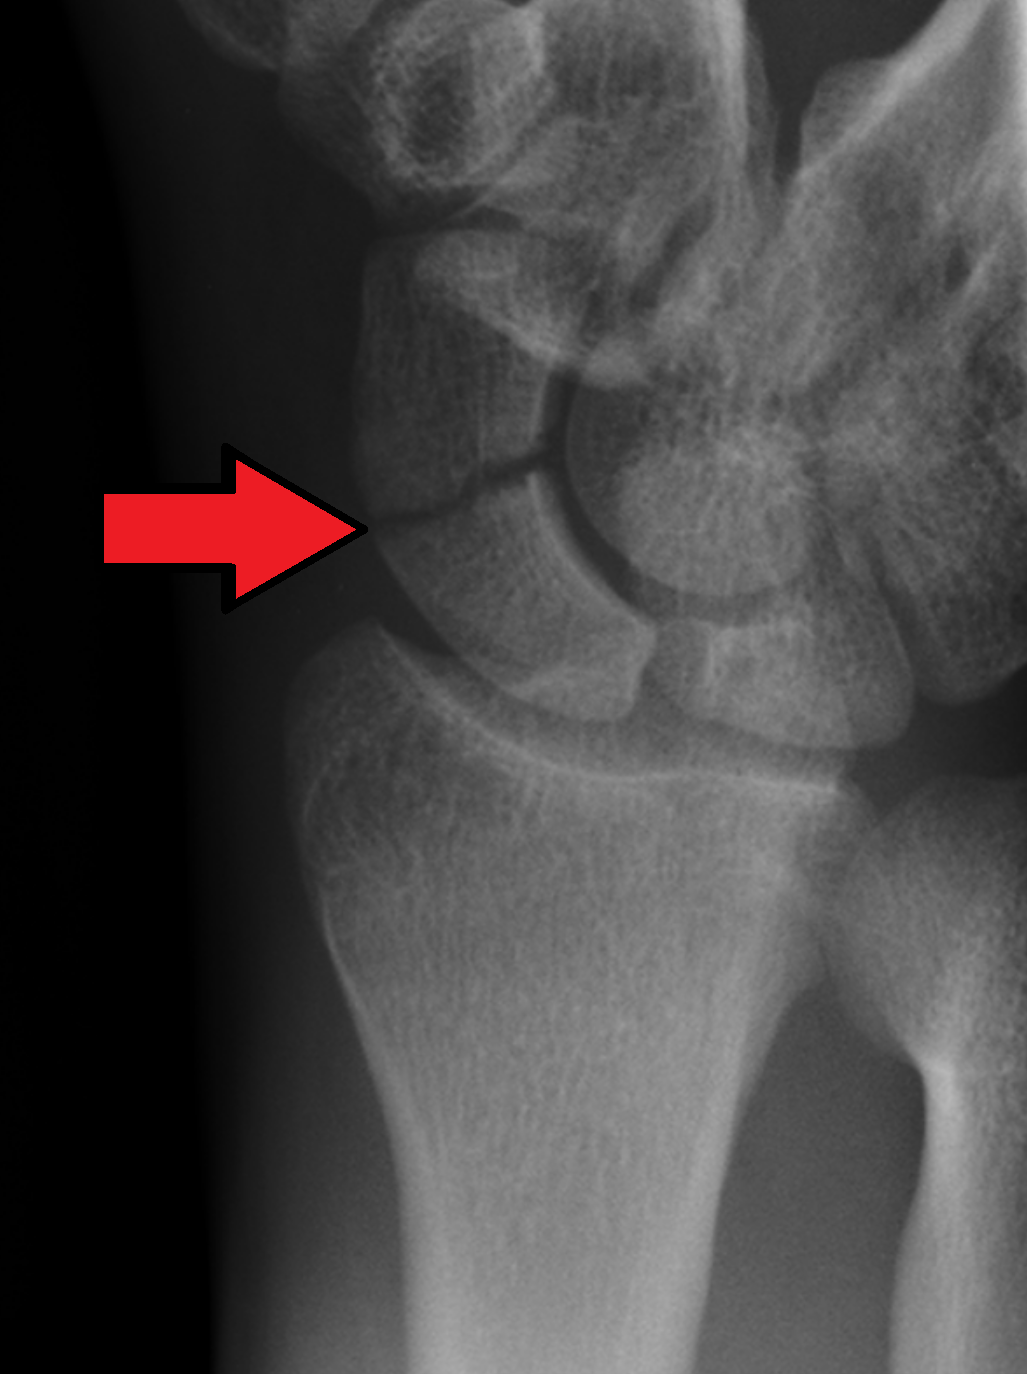

• Scaphoid fracture

• Traumatic history of a fall on an outstretched hand with subsequent anatomical snuff box pain

• High risk of nonunion leading to  advanced collapse and significant disability

• Typically confirmed by x-ray

• Represents 60% of all carpal fractures (7)

• Slowly progressive pain, stiffness, or swelling over the lunate

• Avascular necrosis may affect any of the carpal bones but most commonly involves the lunate (aka Keinbock’s disease) (8)

Standard hand and wrist x-ray images include PA, PA oblique, and lateral views. (12) Additional considerations include:

• A dedicated scaphoid view for patients with a history of trauma or snuffbox tenderness. (13-15)